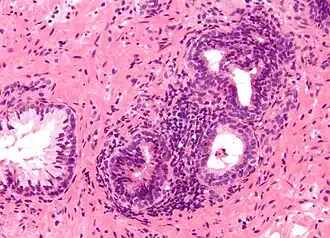

Une prostatite est une inflammation de la prostate. Elle peut être chronique ou aigüe. Une prostatite infectieuse peut être décelée avec le test de Meares et Stamey.